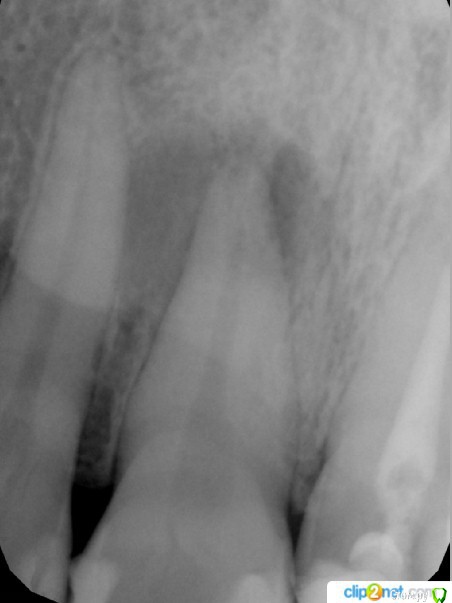

mikedolev Опубликовано 19 апреля, 2016 Поделиться Опубликовано 19 апреля, 2016 Пару лет назад заметил ощущение пульсирования около 11 зуба, спустя неделю оно пропало, несколько раз возникало снова на пару дней и 3 дня назад стало явственно ощущаться в том числе и в течение дня и мешать жить. Боли на холодное-горячее, и накусывание нет. Пошел в ДМС, врач посмотрел снимок (12, 11, 21) и определил что это киста, на его мониторе потемнение было более очевидным и на старом снимке такое же потемнение тоже присутствовало.Программа лечения выбрана "консервативная", в зубе распломбировали канал, промыли заложили пасту Каласепт (если не ошибаюсь в названии), закрыли временной пломбой, через неделю менять пасту и далее каждые 3 месяца такая манипуляция, и возможно через год все нормализуетсяПрошу подсказать верный ли метод лечения выбран, когда (и нужно ли?) задумываться о резекции корня? Ссылка на комментарий

DmitrySH Опубликовано 19 апреля, 2016 Поделиться Опубликовано 19 апреля, 2016 Метод верный, но обычно на такие сроки "Каласепт" не оставляем. 2-3 недели и на второй визит, если нет жалоб, то постоянная пломбировка. Сейчас о резекции задумываться рано. При отсутвии жалоб через 6, 12, 24 мес после лечения сделать контрольные снимки и если эндодонтическое лечение окажется неэффективным, тогда уже резекция. 2 Ссылка на комментарий